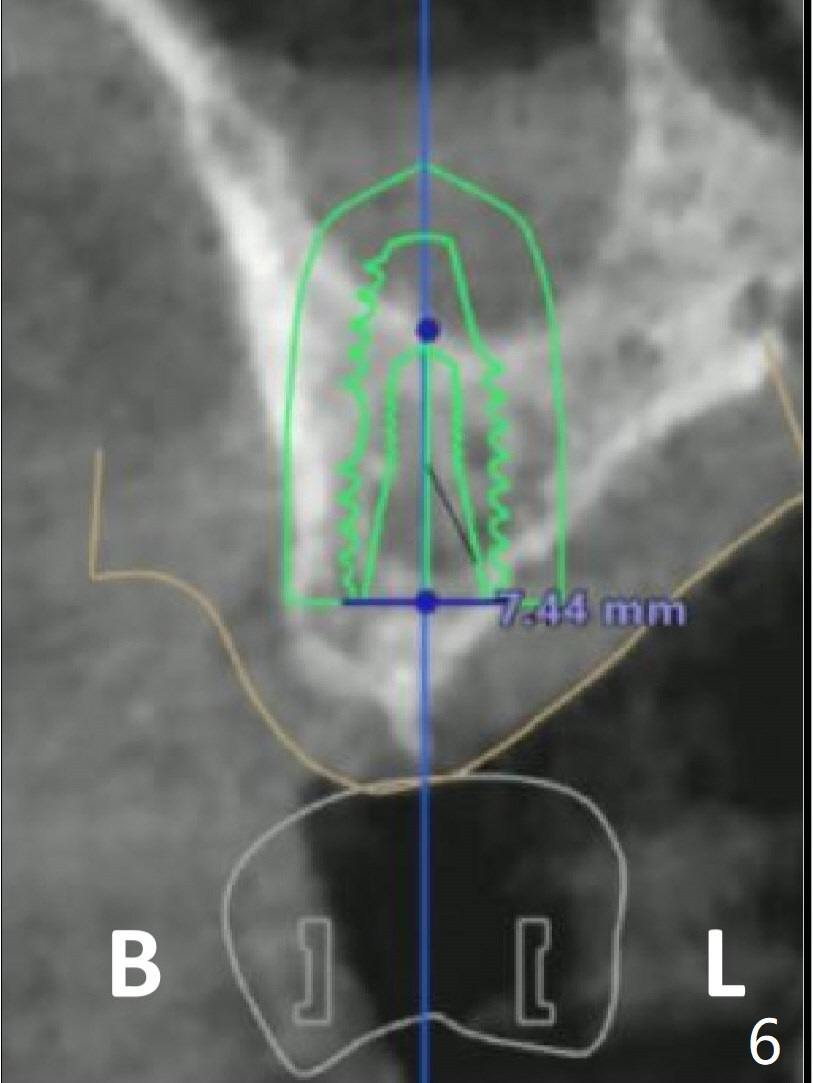

Immediately preop reanalysis of CT shows that there may be palatal thread exposure at #14 when a 4.5x14 mm tissue-level implant is placed equigingival (Fig.1,2). After sinus lift with IS 4x10 mm dummy implant with guide, the tissue-level tap and implant placed free hand look deep (Fig.3,3'). CT reveals possible 3 palatal threads exposed (Fig.4,5 arrowheads), which is associated with change in trajectory due to the palatal shift of the apex of the implant (arrow), as compared to the design of the bone-level implant (Fig.6). When there is a slope in the ridge and/or sinus floor, do not shift implants and use the guide for implant placement. If switching is necessary, use a final drill without underprep (Fig.7 red) through the sinus floor after sinus lift to avoid apical implant deviation. To fix the palatal thread exposure, palatal flap is raised. In fact the implant has to be removed for the incision. When the implant is re-placed deeper by ~ 1mm, there is a thread exposed. Bone graft is placed with collagen membrane. As a 4.5x3 mm abutment is placed, the implant is found to be unstable. Periodontal dressing is applied. In fact the implant exfoliates with the abutment 4.5 months postop (Fig.8). Bone graft seems to be necessary (sticky bone). Tissue level implant should be avoided for patient with poor oral hygiene. Return to Upper Molar Immediate Implant, Trajectory II 3 Xin Wei, DDS, PhD, MS 1st edition 08/30/2019, last revision 05/18/2020